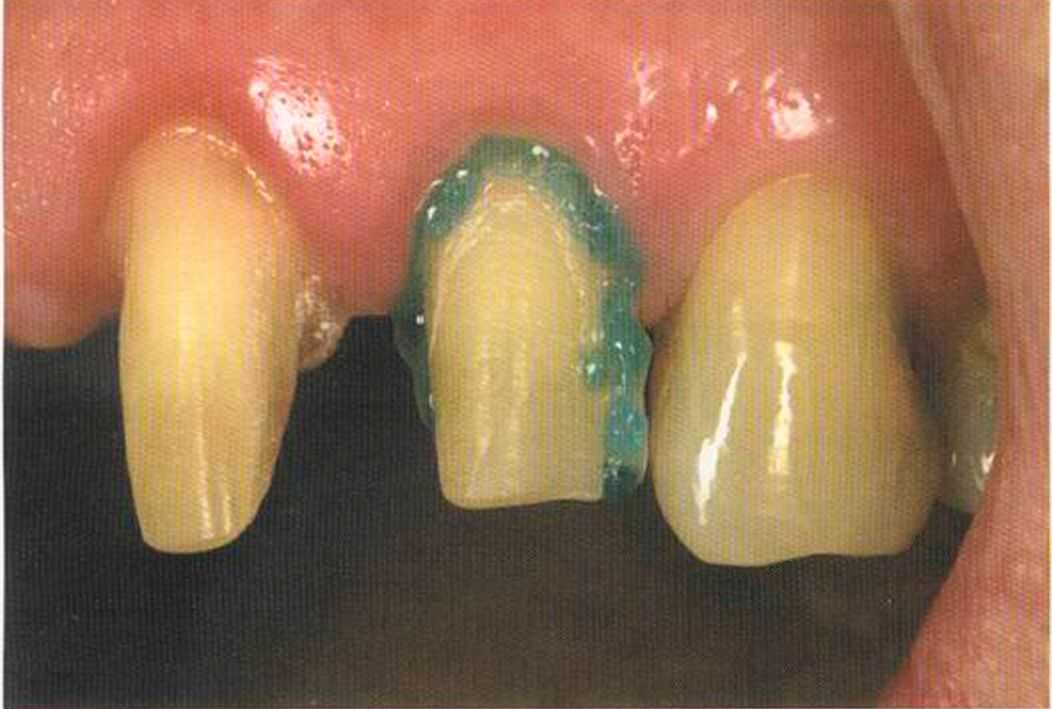

После того как мы определит цвет зуба, решено быо сначсьа изготовить одну коронку.

Результат с использованием In-Ceram развеял все сомнения, и решение об изготовлении коронки на другой боковой резец не заставило себя долго ждать.

Первое лечение проходию много лет назад у другого доктора. Со временем ос те пи / ка уху дин ьась, особенно в пришеечной области. Этот пациент хотел новые коронки в области 12 и 22, по сомневсься, нас кол ько хорошо они будут выглядеть.